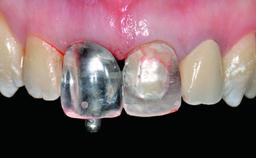

A 28-year-old patient presented at her general dentist’s office and complained about the appearance of her tooth 21. The patient had a history of trauma to this tooth. Endodontic treatment had been performed in the past and a crown placed on the tooth. A procedure to replace the old crown was performed by her dentist; however, a perforation on the middle third of the root occurred, and extraction of tooth 21 was suggested. Upon clinical and radiographic examination of the patient, who had been referred to us, replacement of tooth 21 by a dental implant appeared to be indicated.

Abutment Type Customized